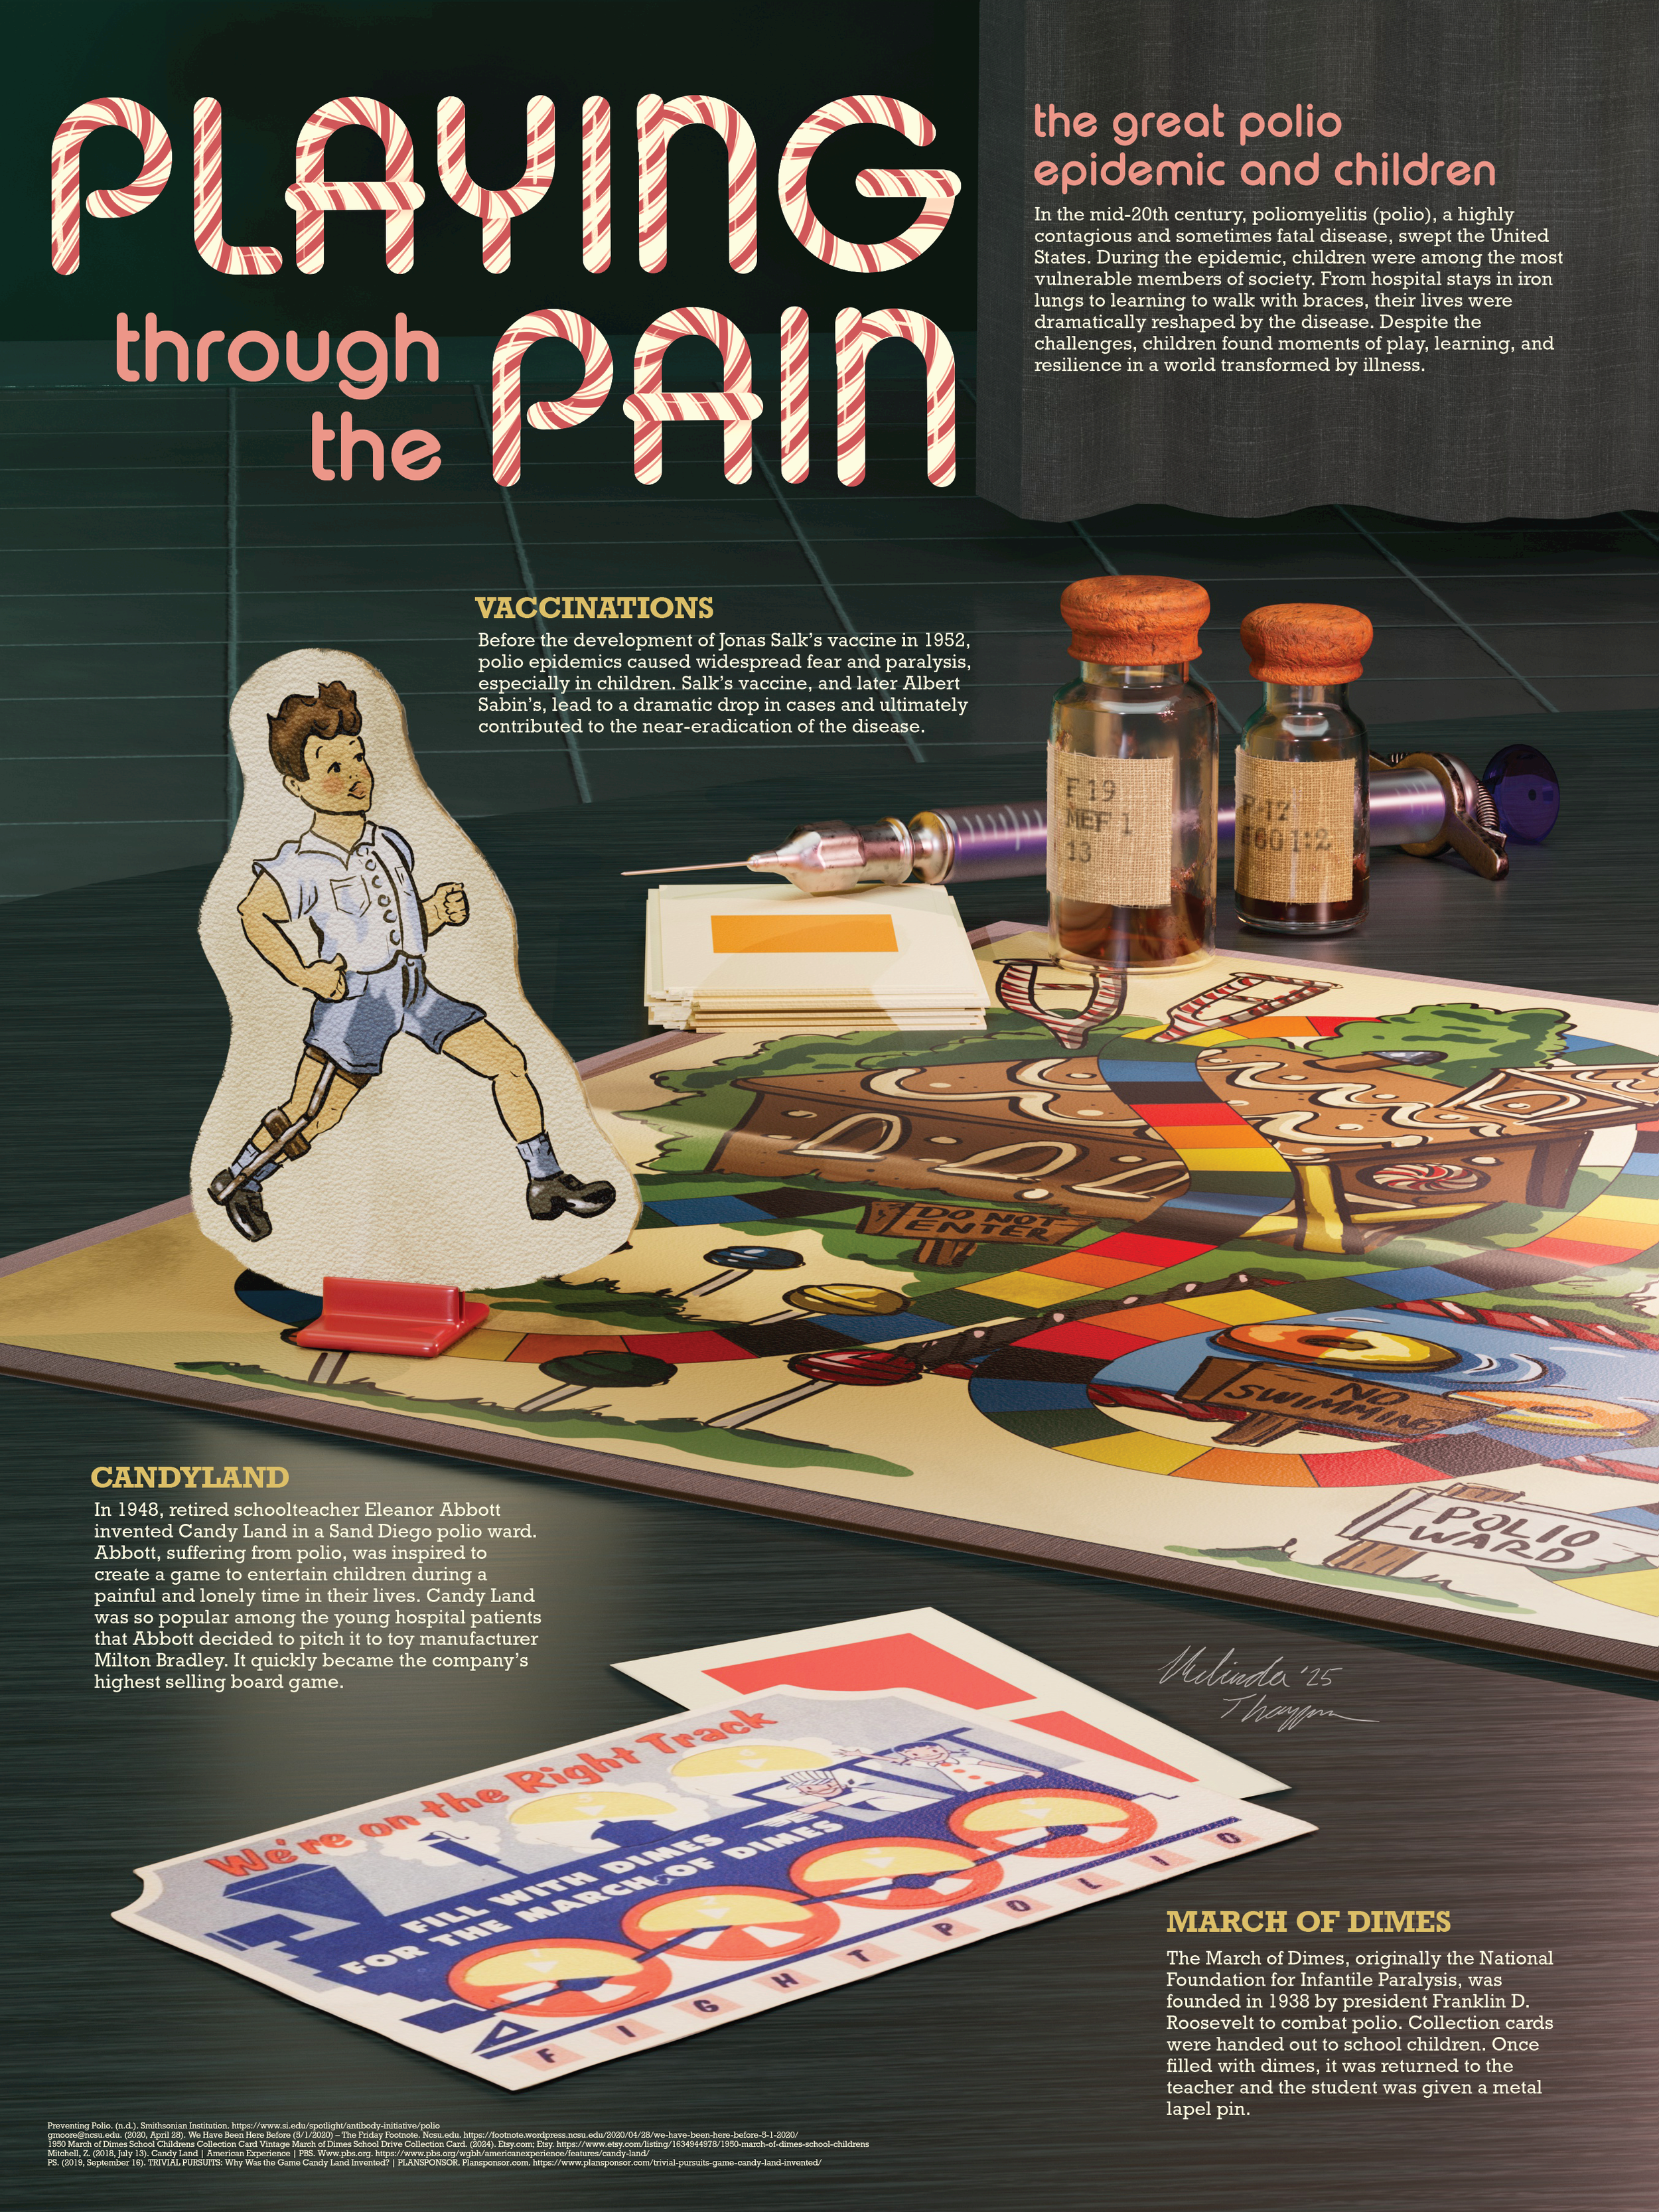

Historical Museum Poster: Playing through the Pain